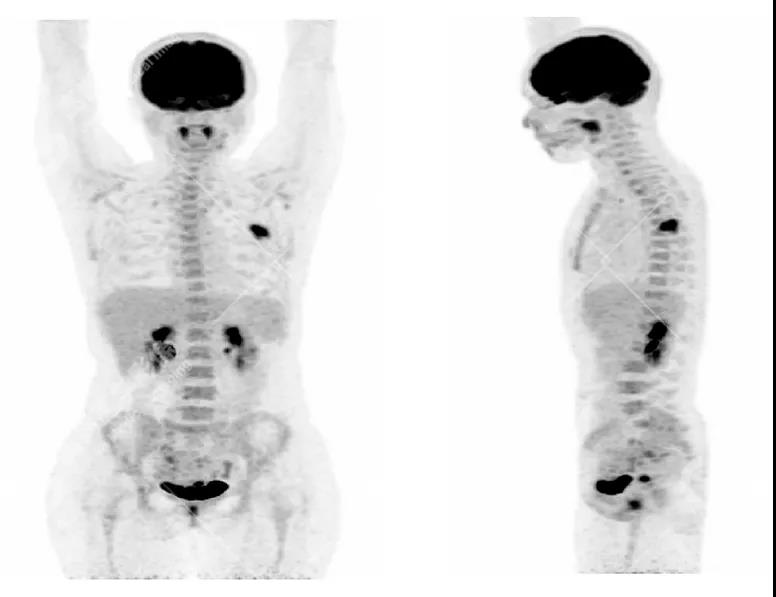

女性 67歲 因背痛查體,糖尿病11年。腫瘤標(biāo)記物:CEA 6.4↑,AFP、CA125、CA199正常。外院MR檢查:胸11椎體-附件左份異常信號(hào),增強(qiáng)環(huán)狀強(qiáng)化,骨原發(fā)?轉(zhuǎn)移?感染?PET/CT影像圖

胸椎溶骨性骨質(zhì)破壞,F(xiàn)DG環(huán)狀代謝增高,SUVmax為4.0。

左側(cè)乳腺一軟組織結(jié)節(jié),F(xiàn)DG代謝增高,SUVmax為2.6。

最終診斷:左側(cè)乳腺癌伴胸椎單發(fā)骨轉(zhuǎn)移。

本次兩個(gè)案例均因單發(fā)骨質(zhì)破壞病灶引發(fā)的骨痛查體,相應(yīng)原發(fā)病灶并無(wú)相應(yīng)臨床癥狀,病灶也不大,若是局部分析,診斷容易受限,難以鑒別。

PET/CT全身排查的優(yōu)勢(shì)在于發(fā)現(xiàn)其它部位隱匿病灶,鑒別原發(fā)與轉(zhuǎn)移灶,提示臨床,得到病理學(xué)支持,這樣能精準(zhǔn)的診斷,從而進(jìn)行下一步有效的治療。